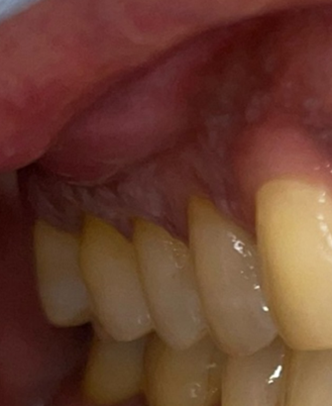

A 62-year-old Middle Eastern female presented to the dental office with the chief complaint of swelling on the buccal mucosa of the posterior right segment (Figure 1). Over the course of 8 months, the patient went to multiple dentists with the initial diagnosis of external root resorption of tooth 1.5 with treatment options including endodontic treatment. Upon clinical examination, the patient presented with persistent vestibulo-buccal swelling in the upper right posterior quadrant. The patient reported pain (Pain Rating Scale score of 6/10) that was initiated 8 months ago, intermittent in frequency, and not exaggerated by external factors. The patient’s health history included Type 2 Diabetes Mellitus and hypertension. The patient’s social history included being a social drinker. There was no family history of cancer. The patient did not indicate any parafunctional habits such as clenching, bruxism, or sleep apnea. Currently, the patient is retired.

Figure 1: Clinical inspection revealed a small swelling in the buccal vestibule of the right maxillary posterior region.